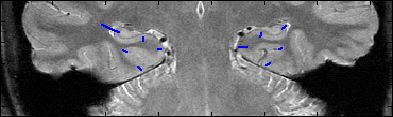

This is an example of one subjects demarcation. The A/P slice is slice

3.

4